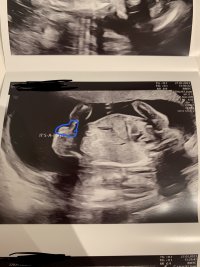

Åja, såpass da misforstod jeg litt Så koselig da Ah skjønner. Ble typisk da

Sant. Da får man jo ting bekreftet. Men

Tenkte mer hvis man hadde handlet inn til spesifikk kjønn og fikk motsatt

Joda. Jeg mente bare at det er vanskelig å føle på sjokk, samtidig som man føler på adrenalinet etter en fødsel

samt utmattet, så jeg greide ikke helt tenke over at "det skulle vært gutt??"